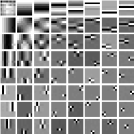

We pre-learn MARS models with different numbers of layers (depths) with transforms. The models are learned from overlapping patches extracted from five XCAT phantom slices. The number of pixels and the number of overall training patches are about and , respectively. The training slices are displayed in the supplement (Fig. 13). The patch stride is . We choose , , , , and layers, respectively, during training, which corresponds to ST, MARS2, MARS3, MARS5, and MARS7 models. We initialize the MARS learning algorithm with the 2D DCT matrix for the transform in the first layer and identity matrices for transforms in deeper layers. For each model, we ran 1000 to 1500 iterations of the block coordinate descent training algorithm to ensure convergence. We choose for ST, , , for MARS2, , , , , for MARS3, , , , , , , , , for MARS5, , , , , , , , , , , , , for MARS7. Fig. 3 shows some of the learned transforms, with each transform matrix row displayed as a square patch for simplicity. The first layer transform in the models typically displays edge-like and gradient filters that sparsify the image. However, with more layers, finer level features are learned to sparsify transform-domain residuals in deeper layers. Nonetheless, the transforms in quite deep layers could potentially be more easily contaminated with noise in the training data, since the main image features are successively filtered out over layers.